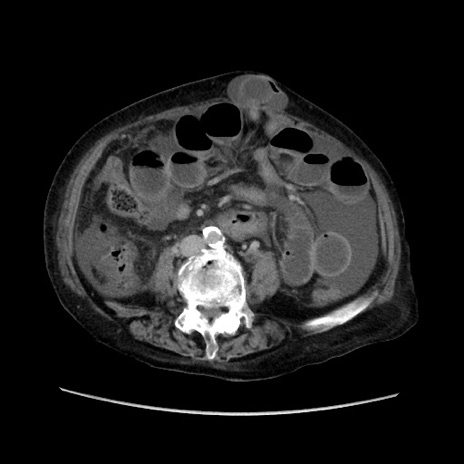

症例31(横断像)

【症例】80歳代 女性

【主訴】腹部膨満感

【現病歴】他院にて肝硬変にてフォロー中。1週間前から便秘、腹部膨満感、臍部腫瘤あり受診となる。

【既往歴】肝硬変

【身体所見】腹部膨隆あり、皮膚変化なし、疼痛なし。

【データ】WBC 4600、CRP 0.25